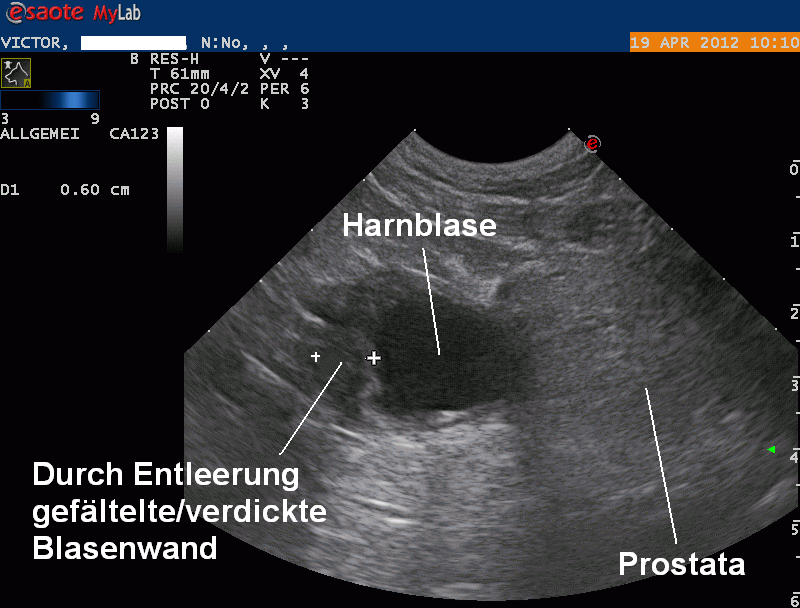

Nach dem Röntgen wird die Bauchhöhle per Ultraschall untersucht: Die Blase enthält nur wenig Urin; dadurch erscheint die Blasenschleimhaut im vorderen Blasenteil verdickt und aufgefältelt. Eine Geschwulst in diesem Bereich kann jedoch, obwohl von der Lokalisation her sehr unüblich, nicht komplett ausgeschlossen werden. Aus der Blase wir mit einer Kanüle Urin entnommen - die mikroskopische und bakteriologische Untersuchung zeigt, dass weder ein bakerieller Infekt, noch eine Entzündung in der Blase vorhanden ist.